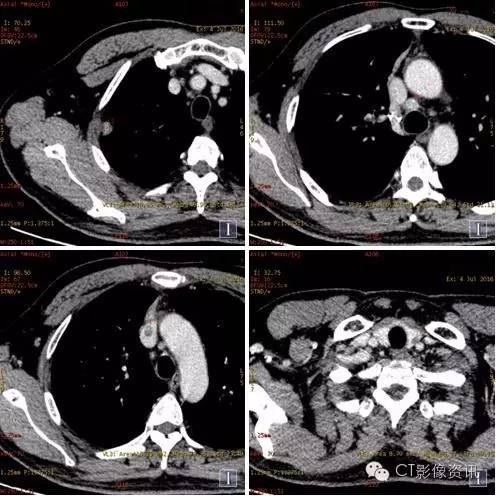

扫描方法 能谱平扫及两期增强扫描。病理已提示右上肺癌纵隔淋巴结转移;上腔静脉病灶为癌栓?血栓?左甲状腺病灶为转移?原发病灶? 常规平扫及静脉期

常规图像及碘基图均显示上腔静脉病灶明显强化。

常规平扫及强化两期

常规图像及碘基图显示病灶轻度强化。